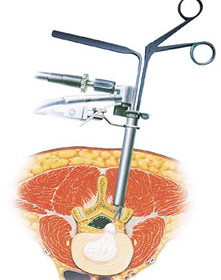

脊椎内視鏡下椎間板摘出術・椎弓切除術

脊椎の後方から直径1.6 cmの管を挿入して、内視鏡カメラで術野をモニターで確認しながら、椎間板ヘルニアを摘出する、あるいは脊柱管狭窄の原因となっている骨や靱帯などの組織を摘出して神経の圧迫を取り除く方法です。和歌山県立医科大学整形外科では1998年に吉田宗人第5代教授が日本国内で先駆けて脊椎内視鏡下椎間板摘出術(MED法)を導入し、以来新たな技術の開発と安全性の確立に尽力して来ました。この手術技術を学ぶために、国内外から多くの医師が見学に訪れると共に、医師向けの教科書も出版されています。現在では椎間板ヘルニアだけでなく、腰部脊柱管狭窄症、頚椎症性脊髄症・神経根症にも脊椎内視鏡下手術が安全に実施可能となっています。通常、術中出血量は30 ml 以下で、術後5日目からの退院が可能となります。

椎間板ヘルニアに対する

MED法

脊柱管狭窄に対する

片側進入両側除圧法